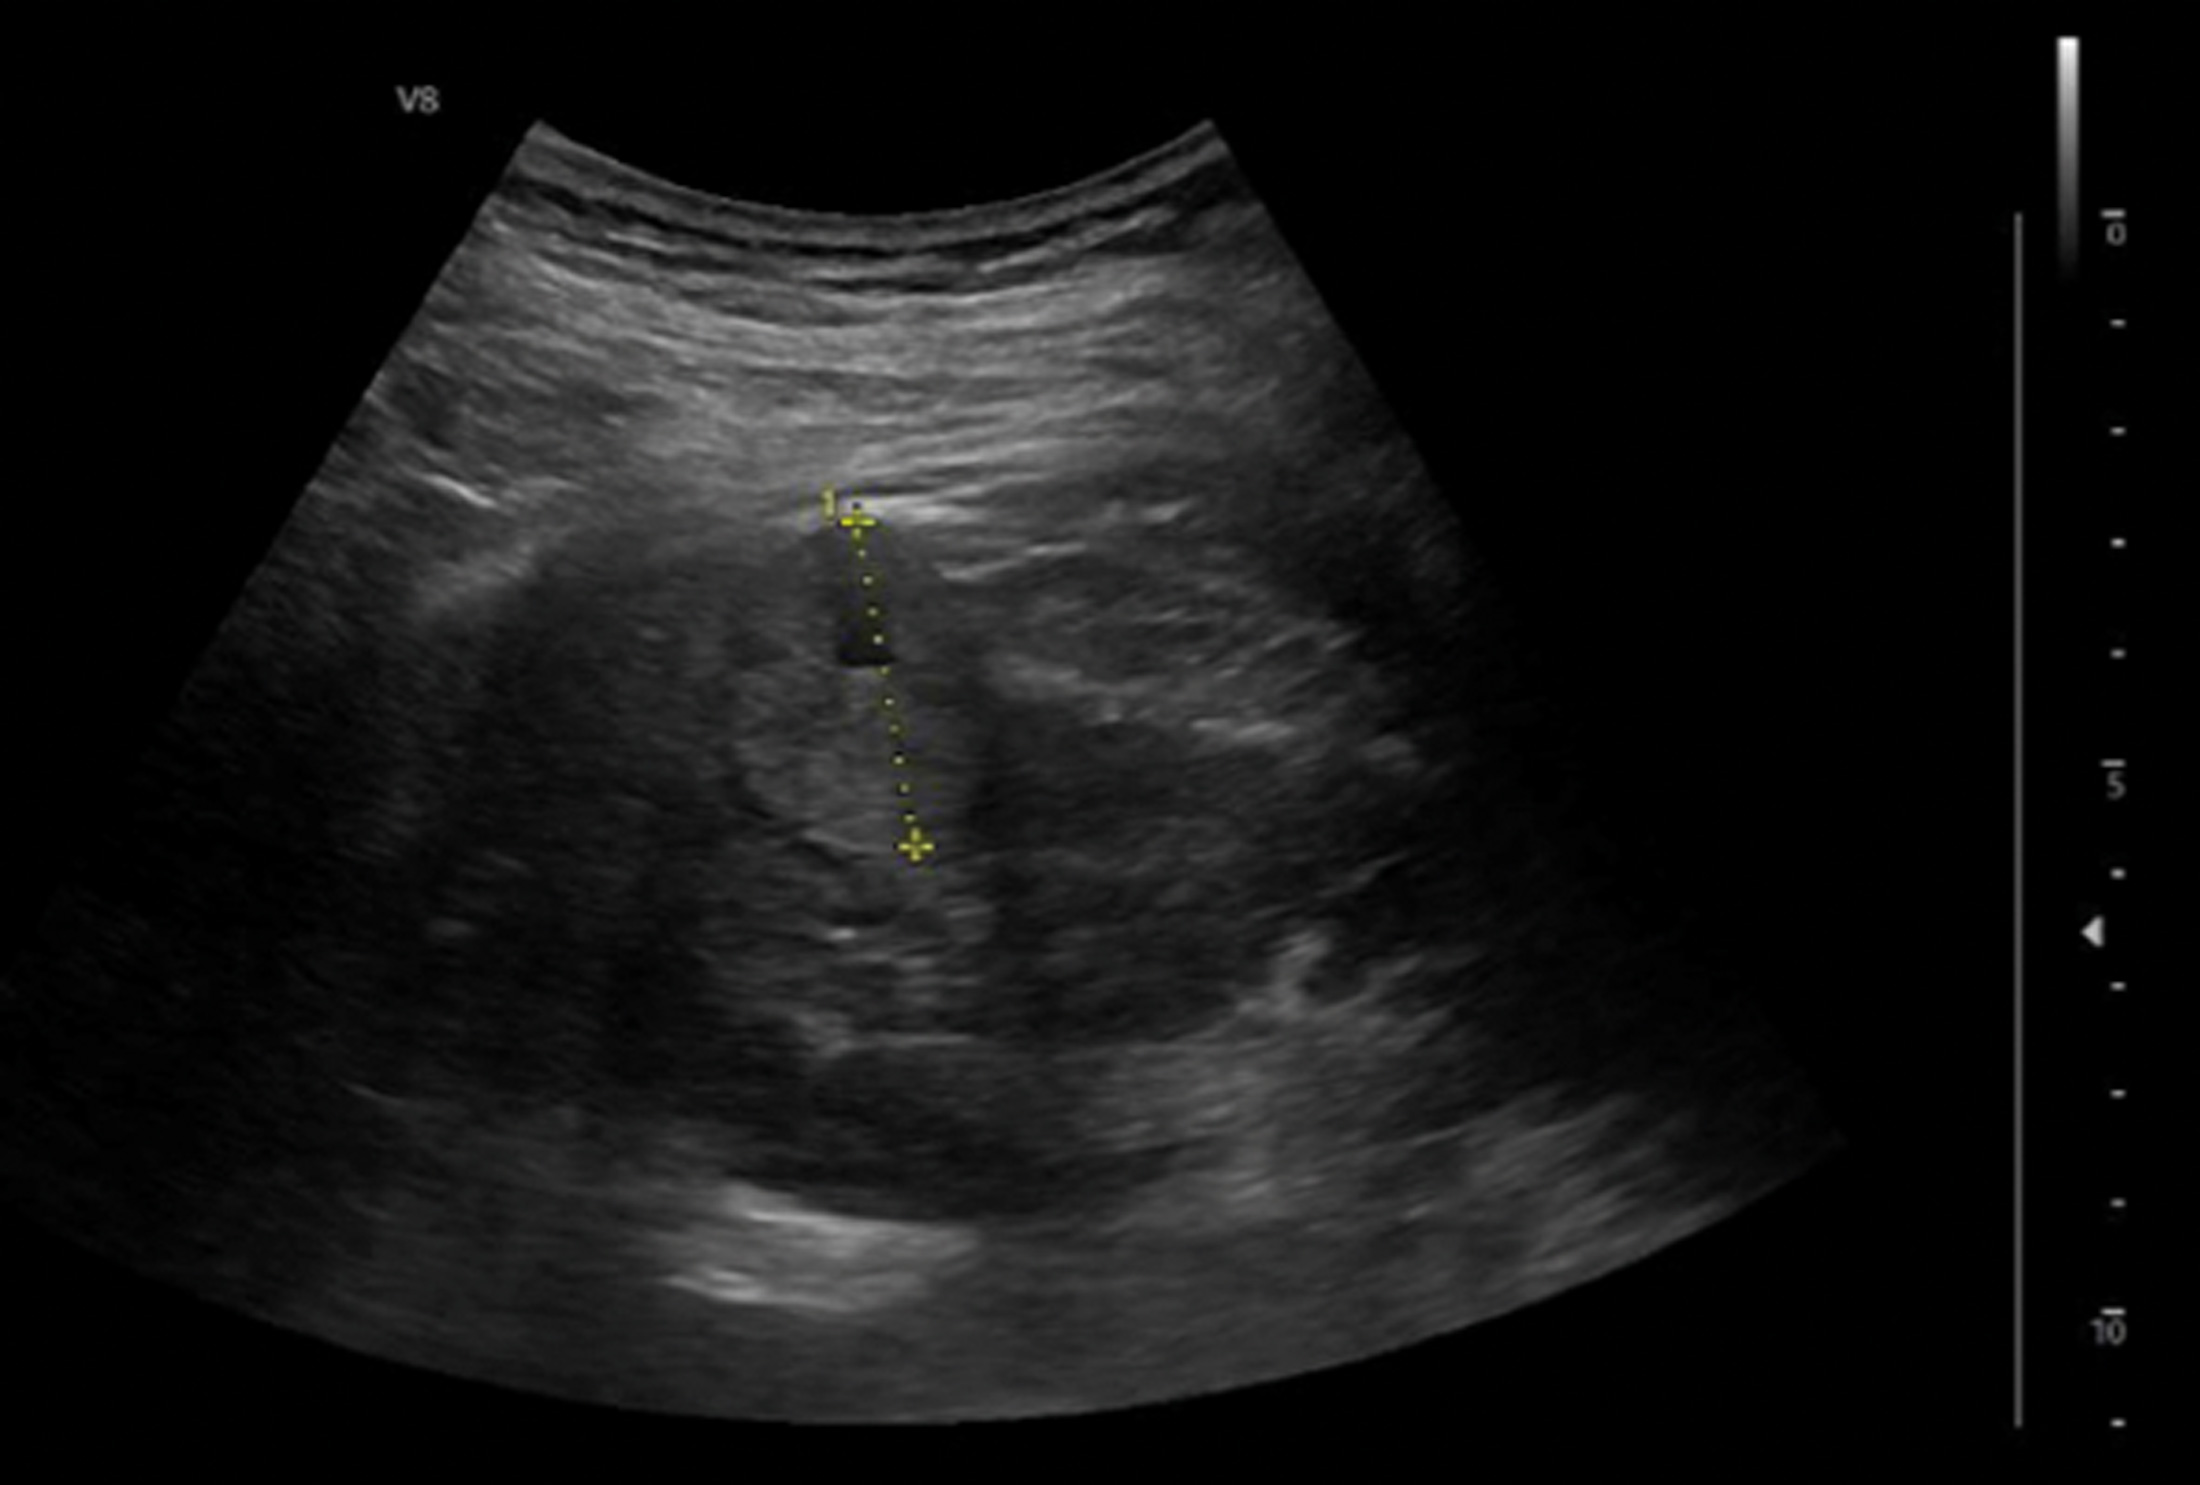

Case 1

A 56-year-old lady is referred to the urology clinic after the GP conducted an ultrasound abdomen for deranged liver function tests and found a renal lesion. She is otherwise fit and well.

Figure 1.

1. Sensitivity of US in detecting renal masses depends on the size of the lesion. Sensitivity for tumours >3cm and smaller tumours (2-3cm) is reported to be 85-100% and 67-82% respectively [1]. Plain US typically looks for distortion of architecture. Doppler US identifies increased vascularity to an area relative to the surrounding tissue, which is particularly useful for endophytic tumours and in differentiating between RCC and small angiomyolipomas (AML). Another modality is contrast-enhanced US (CEUS), which identifies areas of renal parenchyma brightness and can assess for microcirculations. CEUS has a suggested sensitivity up to 95% and specificity around 55% [2]. They can help demonstrate hypovascular lesions such as papillary RCC, but may not differentiate RCC from oncocytoma / AML [3].